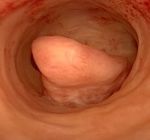

Endometrial Polipler

Rahim duvarının iç tabakasından, rahim boşluğuna uzanan, parmaksı çıkıntılardır. Hormonal etkilerin sonucunda görülebilir. Bu yapıların doğurganlık üzerindeki etkisine ilişkin veriler sınırlı olmakla birlikte, özellikle büyük boyuttaki poliplerin çıkarılması önerilmektedir.